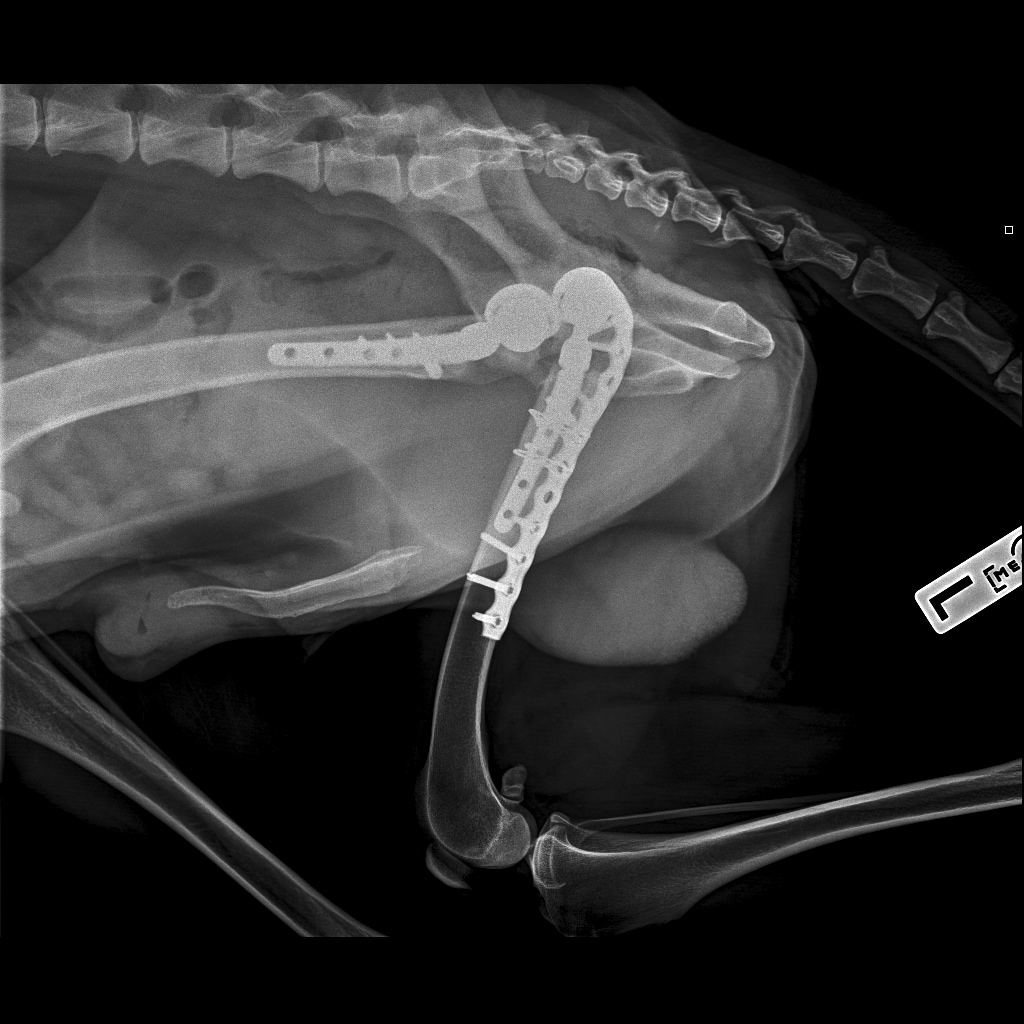

Выписка